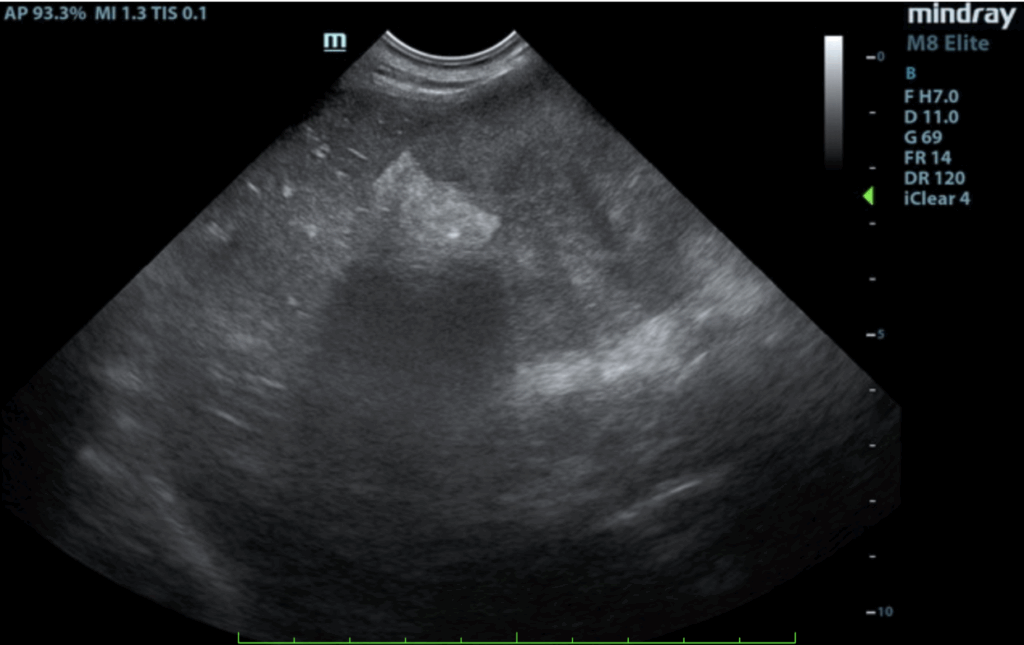

Spleen:

The spleen revealed an expansive parenchymal mass that measured 10+ cm without evidence of cavitation. Hyperechoic fat was noted around the spleen. This is consistent with inflammation.

Free Abdomen:

A slight amount of free fluid was noted.